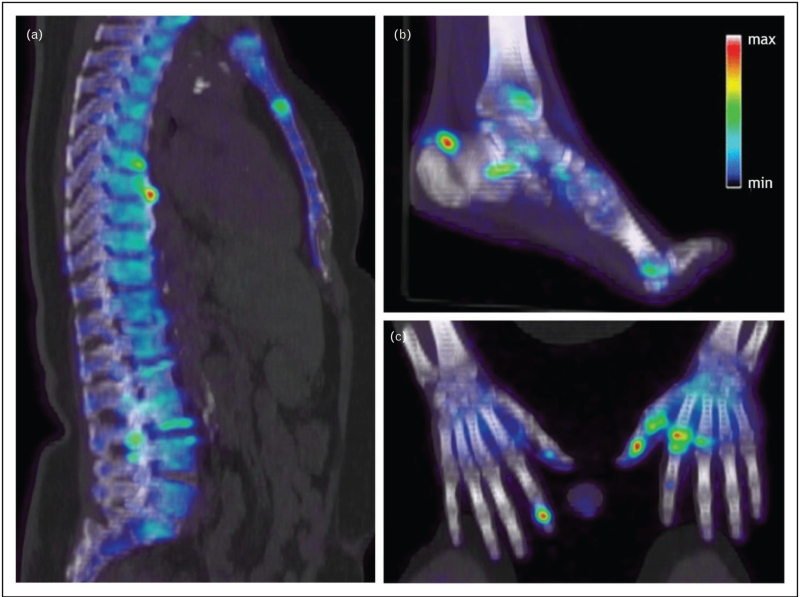

Purpose of review: Psoriatic arthritis (PsA) is a chronic inflammatory disease associated with psoriasis. Conventional imaging techniques are used to diagnose the disease and detect long-term structural changes. This review will assess molecular imaging in PsA, to evaluate its potential additive value over conventional and advanced anatomical imaging methods (e.g. ultrasound and MRI).

Recent findings: Current research is primarily focused on the molecular imaging technique PET/computed tomography (PET/CT) imaging, in which different tracers have been investigated. Fluorodeoxyglucose (FDG) can visualize disease activity and subclinical inflammation. New tracers targeting inflammatory sites have also been studied, such as FAPI (fibroblast activation protein inhibitor). Moreover, NaF (sodium fluoride) shows promise for imaging of new bone formation. Next to PET/CT, also fluorescence imaging and multispectral optoacoustic tomography have been investigated in the context of PsA.

Summary: Molecular imaging techniques hold promise for early diagnosis, monitoring and management of PsA. Future research is needed to define the role of molecular imaging relative to conventional and anatomical imaging techniques in patient care.